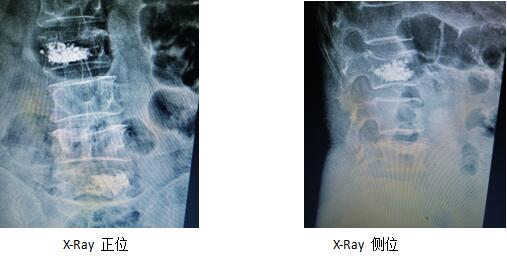

術(shù)后復(fù)查片(骨水泥彌散均勻,無(wú)外漏)